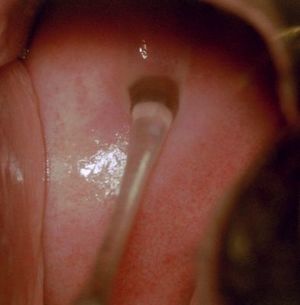

صورة توضح إفرازات المهبل عند الإثارة

يبطن المهبل من الداخل بشرة فريدة من نوعها غنية بمادة الغليكوجين، وهي بشرة رطبة غنية بالإفرازات. المصدر الأساسي لهذه الإفرازات هي ارتشاح السوائل من الدورة الدموية واللمفاوية عبر جدار المهبل. تؤدي إفرازات عنق الرّحم دورها بالمشاركة مع إفرازات المهبل إلى ترطيب جوف المهبل وتسهيل عملية الإيلاج خلال العملية الجنسية. إفراز هذه السوائل المرطبة والمزلقة يأتي كرد على التحريض الهرموني، والإثارة الجنسية، وعندما يتوقف نشاط المبيض يخف مقدار هذه الإفرازات فتشعر السيدة بالجفاف.

صورةالتقطت بواسطة منظار الرحم تبين الإفرازات المهبلية البيضاء الطبيعية والتي تتوضع على عنق الرحم وعلى جدار المهبل.

تقوم الغدد داخل المهبل وعنق الرحم بإفراز كميات صغيرة من السائل. هذه التدفقات من السائل تشطف المهبل كل يوم، حاملة معها الخلايا القديمة والميتة التي كانت في الاصل خلايا مبطنه للمهبل. وهي طريقة الجسم في تنظيف المهبل وأبقاءه صحيا. الافراز عادة يكون صافيا إلى حليبي لكنه يكون بدون أي رائحة سيئة.

لون وسماكه الافراز يتغير مع الدورة الشهرية. فالافراز يصبح أكثر كثافة عندة فترة التبويض (عندما تقوم إحدى المبايض بإفراز البويضة)، وعند الارضاع من الثدي، أو عند الاثارة الجنسية.